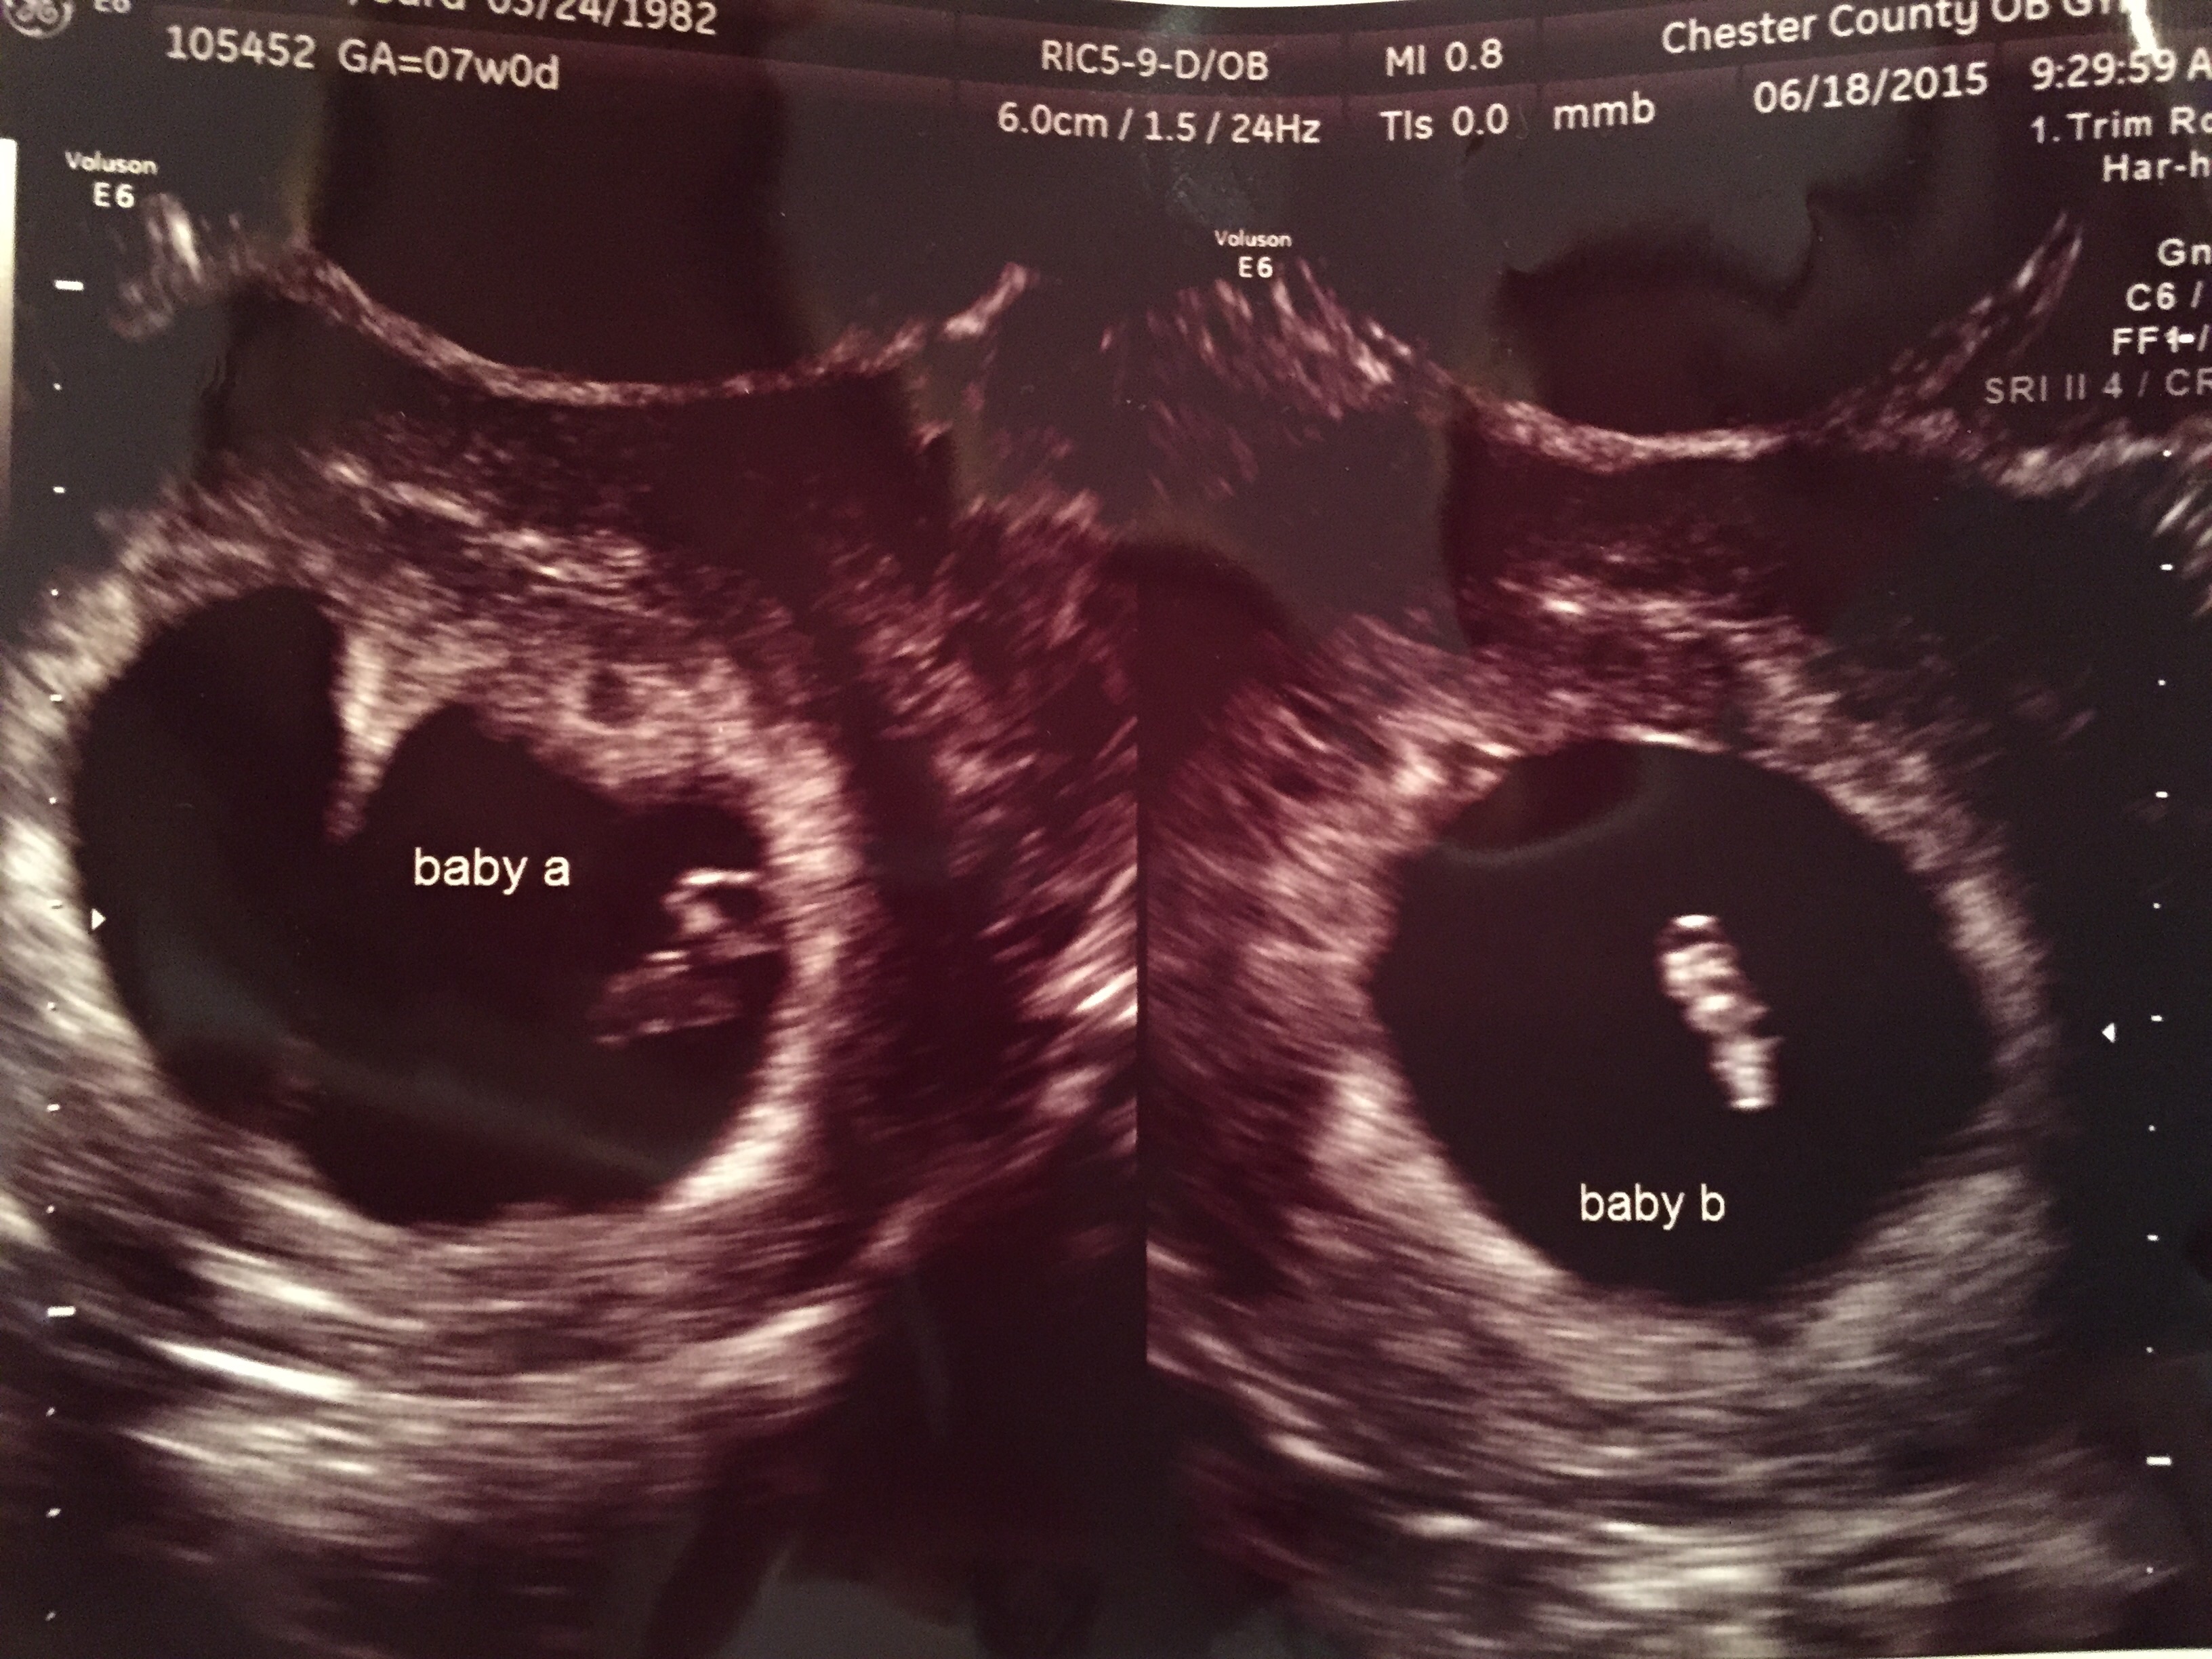

So I had my first ultrasound today...

Needless to say I'm a little shocked!